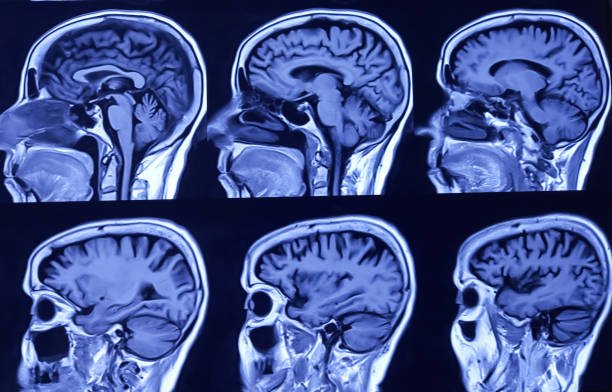

Traumatic Brain Injury

Traumatic brain injury rehabilitation enhances cognitive function, mobility, independence, and quality of life through specialized therapies.